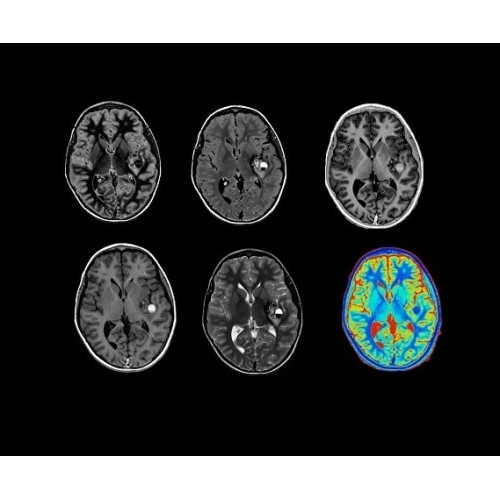

SIGNA PET/MR 3.0T — это гибридная система, в которой совмещаются две принципиально разные технологии — магнитно-резонансную томографию (МРТ) и позитронно-эмиссионную томографию (ПЭТ). Система отличающийся высокой чувствительностью и эффективностью и предназначена для диагностики в области онкологии, неврологии, кардио-васкулярных исследований, исследований воспалительных процессов.

Компания GE Healthcare представляет революционную, полностью интегрированную систему SIGNA PET/MR1, в которой сочетаются времяпролетная технология (TOF) и возможности напряженности магнитного поля 3.0 Тл. Мы поможем вам поднять исследования на более высокий уровень. SIGNA PET/MR позволяет достичь впечатляющей точности и скорости исследований, а благодаря новейшей технологии реконструкции Q.Clear2 качество изображений улучшается в два раза. Кроме того, в систему включен полный набор клинических приложений и гибких катушек для проведения любых видов исследования, открывая для вас возможности визуализации, о которых вы даже не догадывались.

Система SIGNA PET/MR предлагает впечатляющие клинические возможности и открывает доступ к наиболее полным пакетам программных приложений.

Стандартный пакет приложений SIGNA Works позволит вам достичь желаемых результатов в клинической практике благодаря набору высокоэффективных средств визуализации. Программные приложения, входящие в состав данных клинических пакетов, включают широкий спектр контрастов, функции обработки 2D- и 3D-данных, а также возможность коррекции артефактов движения. SIGNA Works предоставляет набор инструментов, необходимых для проведения эффективного клинического исследования.